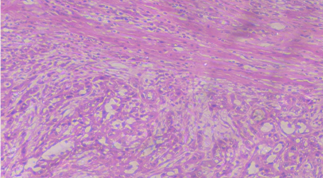

Histopathology of OSCC (Oral Squamous Cell Carcinoma) samples was done to grade them according to their differentiation. Histopathology was not only done to grade the tumor tissues but also used to get an idea about the prognosis or aggressiveness of disease. For histopathological grading of cases, 50-60 mg of OSCC (Oral Squamous Cell Carcinoma) tissue samples is obtained and put in formal saline. Parts were first embedded in paraffin wax; then tissue blocks were created and sliced into thin, uniformly cut sections using a microtome. The pieces were then placed on slides and stained with hematoxylin and eosin (fig. 1).

All the OSCC (Oral Squamous Cell Carcinoma) patients were graded clinicopathologically and histopathologically in various categories to keep an estimate about the aggressiveness and prognosis of the patient. Patients were histopathologically graded according to their differentiation into Well-differentiated tumors, i.e. Grade I and Moderately and poorly differentiated tumors, i.e., Grade II and we found that a little more than half of the patients recruited were in Grade I. Majority of tumors were located on the buccal mucosa (63.5%), 32% were located on tongue and only 9% were found on upper and lower gingival crevices. Around 80% of the patients were in early stages of OSCC (Oral Squamous Cell Carcinoma) with little or no lymph node involvement and rarely, we found any cases with distant metastasis (table 1, fig. 1A-D).

Fig. 1A: Well-differentiated oral squamous cell carcinoma

Well-differentiated tumors characterized by the presence of keratin islands with keratin pearls inside. Inside the keratin pearls, the cells are acidophilic with pyknotic nucleus and karyolysis.

Fig. 1B: Moderately differentiated oral squamous cell carcinoma

Moderately differentiated tumors are characterized by the presence of organized islands of neoplastic cells. At the periphery, the islands are separated with inflammatory cells. Tumor cell nuclei have different shapes and sizes.